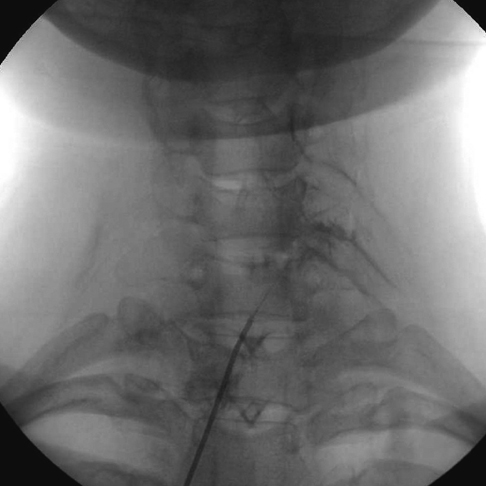

Clinical Outcomes of Epidural Neuroplasty for Cervical Disc Herniation

- Cervical disc herniation is a common disorder characterized by neck pain radiating to the arm and fingers as determined by the affected dermatome. This condition has a favorable prognosis, but pain can have a serious detrimental impact on daily activities. Epidural neuroplasty has been applied as a treatment option for cervical disc herniation; however, no study has addressed the clinical outcomes. This retrospective study evaluated the clinical outcomes of epidural neuroplasty on 128 patients for the treatment of cervical disc herniation. To measure pain-related disabilities over time, the changes of pain scores in neck and arm were evaluated using a numerical rating scale (NRS) and the neck disability index (NDI). Compared with preprocedural values, the pain NRS of neck and arm demonstrated significant improvement at day 1, and 1, 3, 6, and 12 months after the procedure (P < 0.001). Likewise, the NDI was significantly reduced at 3, 6, and 12 months after the procedure (P < 0.001). There were no serious complications. Cervical epidural neuroplasty shows good clinical outcomes in the treatment of cervical disc herniation and can be considered a treatment modality for cervical disc herniation refractory to conservative treatment.

Cervical Vertebrae/*radiography

Epidural Space/radiography